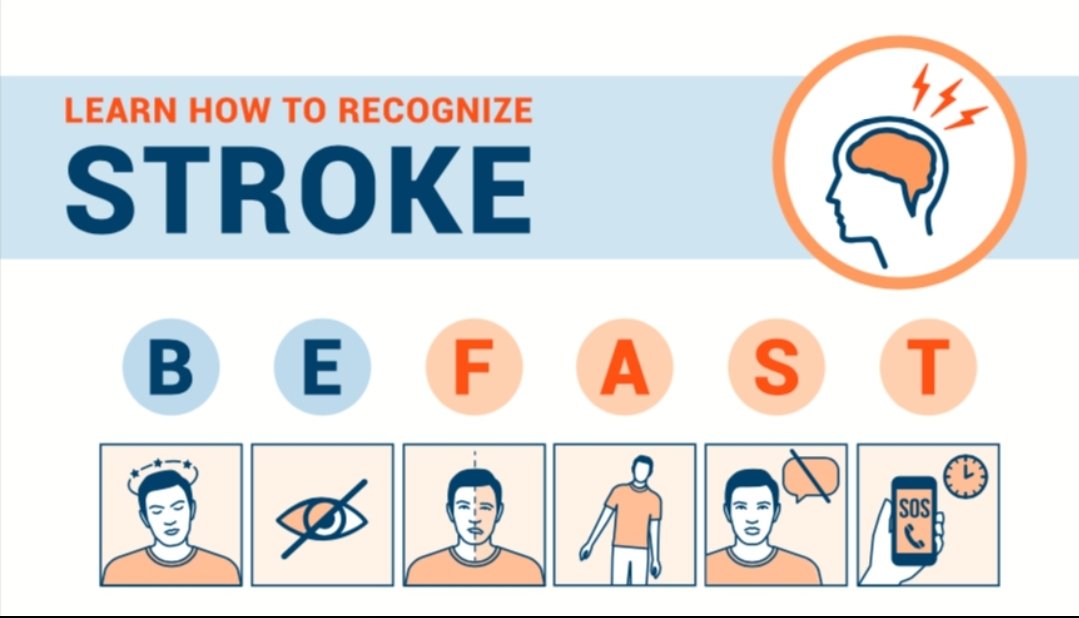

💥أعراض #السكته_الدماغيه بنوعيها

سر التشخيص كلمتين

🔑تغير #مفاجئ

🔑في #نتعاجل او #عاجل (الاعراض)

ن👁️نظر

ت🚶♂️توازن

ع🤐عسر في الكلام

ا😏انحراف في الفم والوجه

ج🦽جانب من الجسم لايتحرك او يحس

ل📞🚑لاتتردد

اتصل ب 911 واذهب لاقرب مركز متخصص

فيديو توعوي

كيف تتصرف إذا رأيت

💥احد أعراض #السكته_الدماغيه بنوعيها

المختصره في كلمه #نتعاجل او #عاجل

ن👁️نظر

ت🚶♂️توازن

ع🤐عسر في الكلام

ا😏انحراف في الفم والوجه

ج🦽جانب من الجسم لايتحرك او يحس

ل📞🚑لاتتردد اتصل ب 911 واذهب لاقرب مركز متخصص